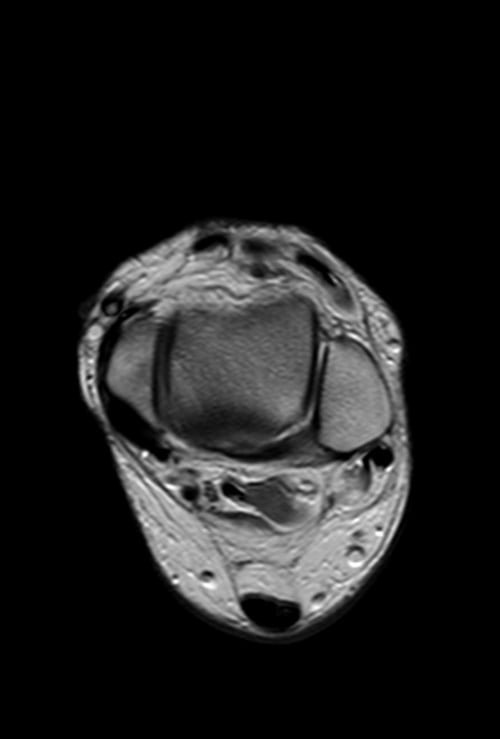

MRI ANKLE AXIAL PD IMAGE 2 - MRI